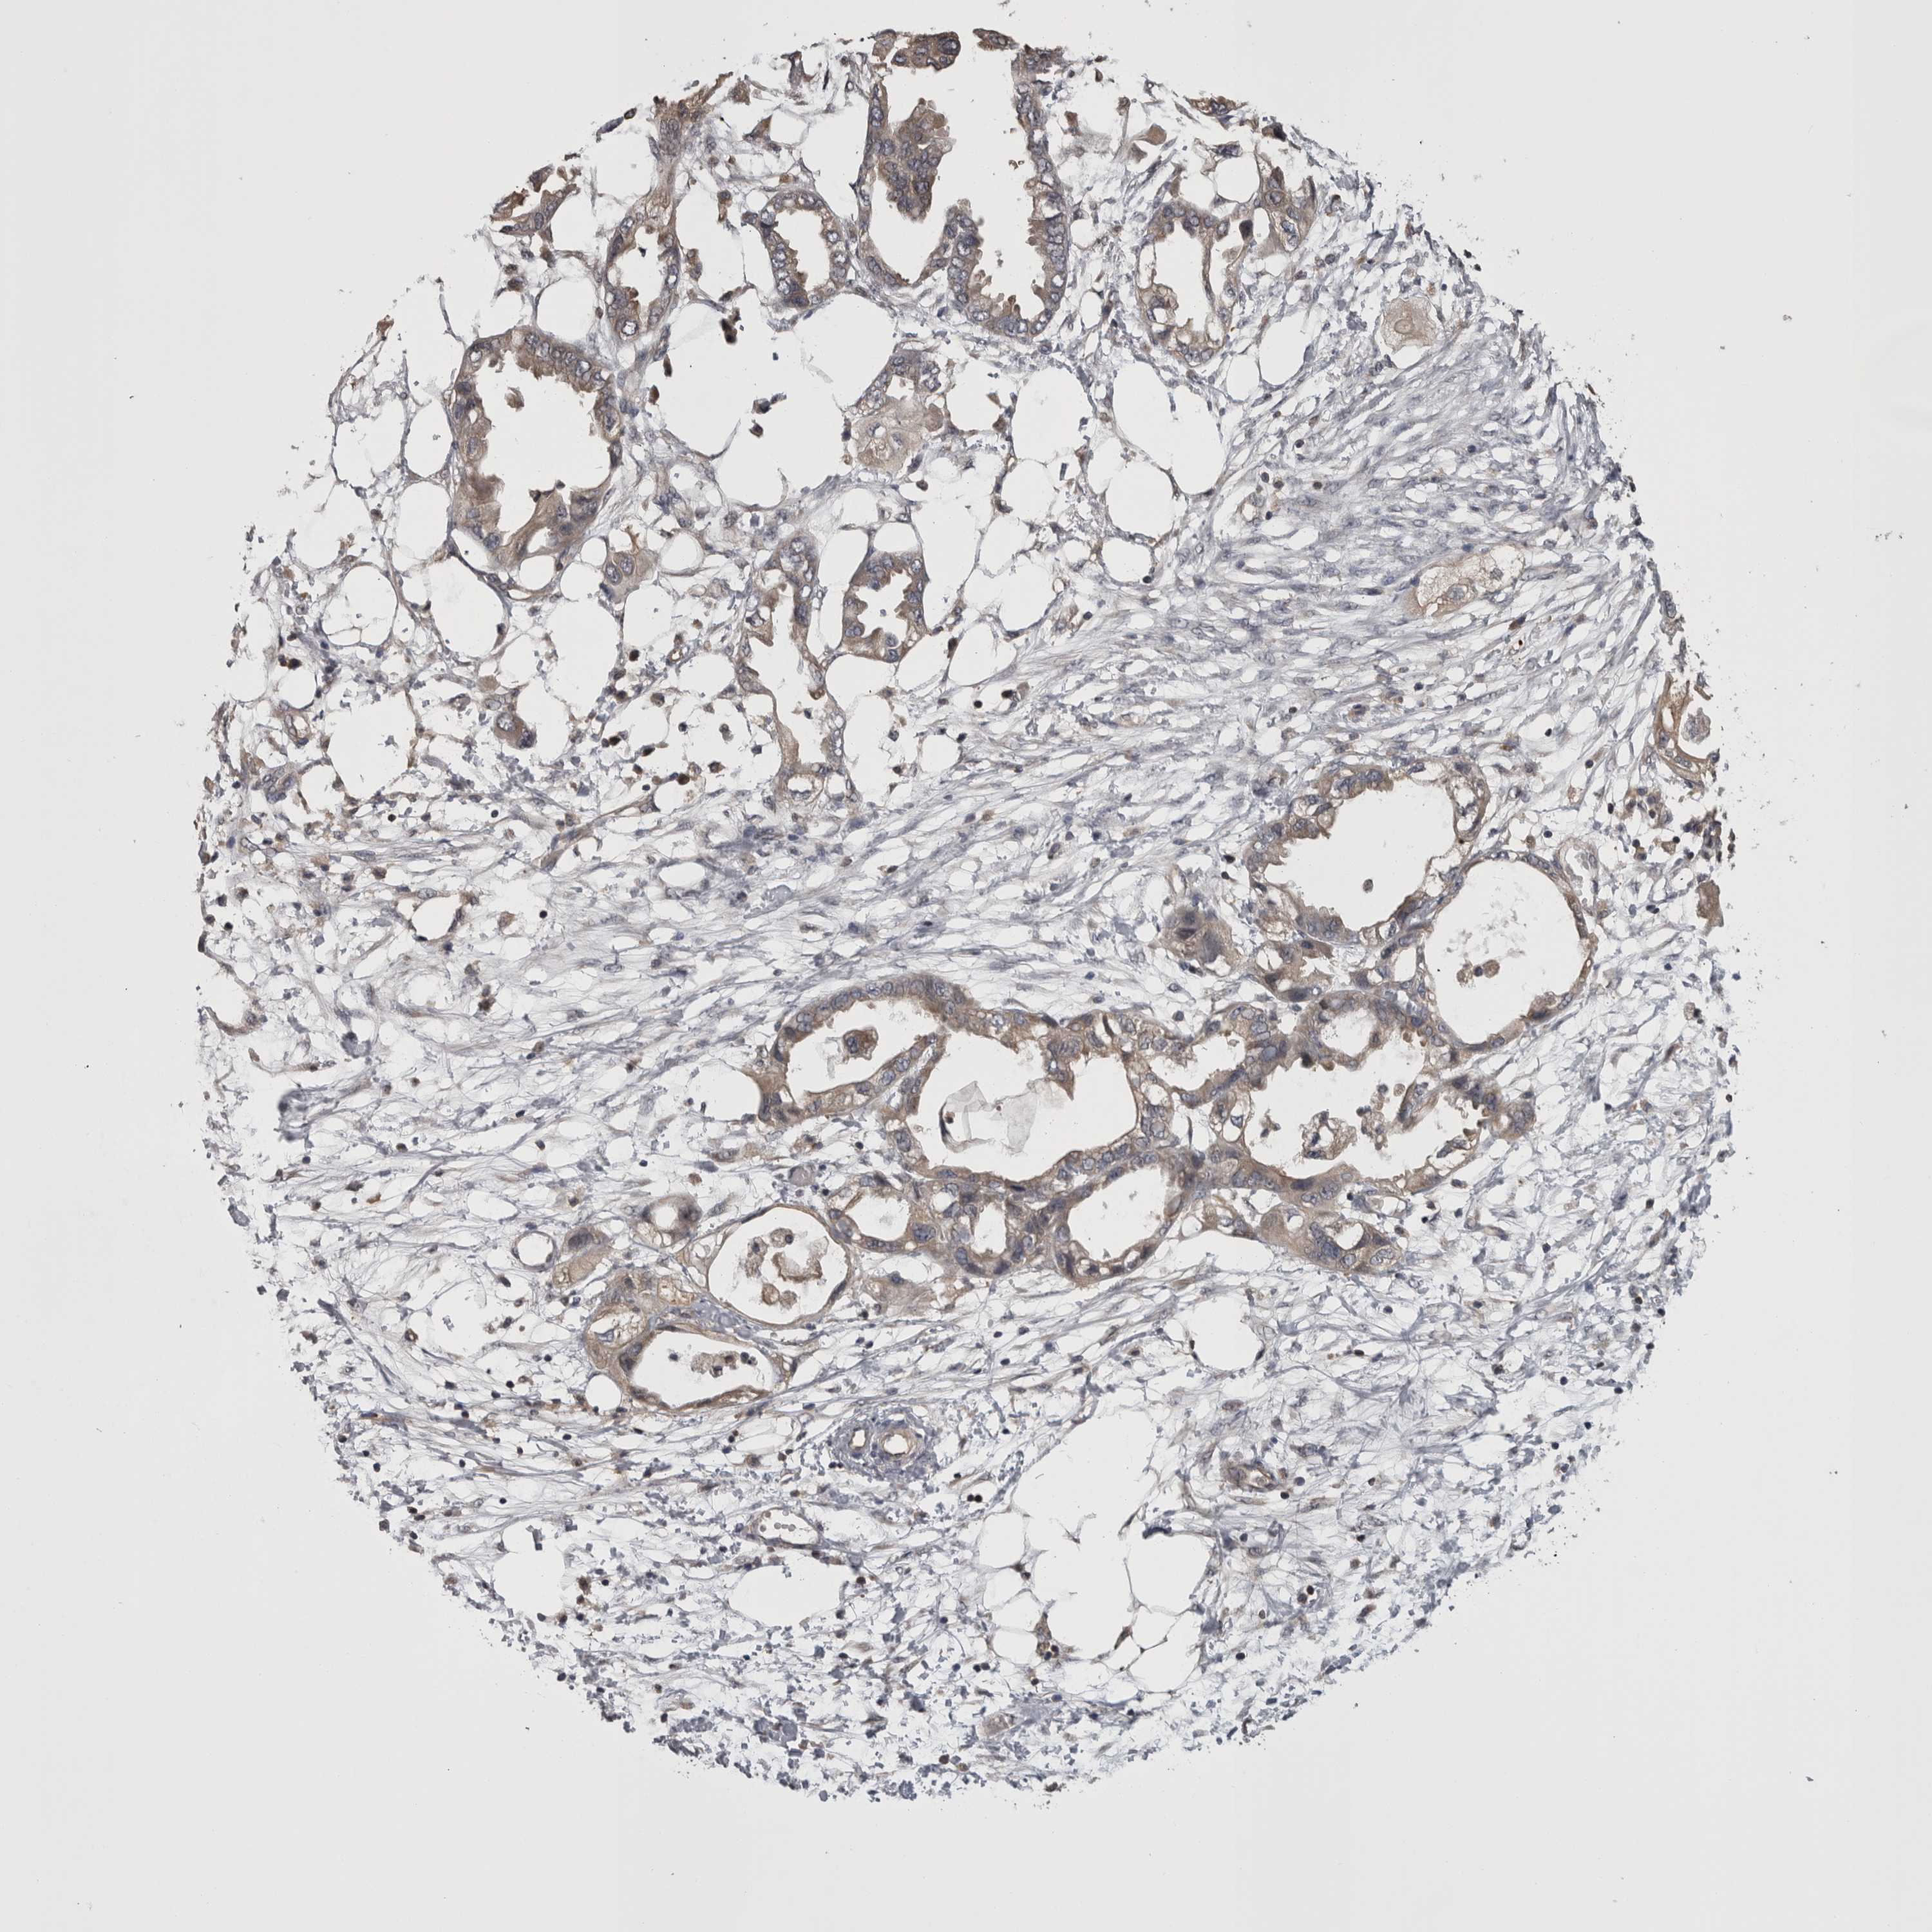

ENDOMETRIAL CANCER - Protein expressioni

A mouse-over function shows sample information and annotation data. Click on an image to view it in a full screen mode. Samples can be filtered based on level of antibody staining by selecting one or several of the following categories: high, medium, low and not detected. The assay and annotation is described here.

Note that samples used for immunohistochemistry by the Human Protein Atlas do not correspond to samples in the TCGA dataset.

Antibody stainingi

Antibody staining in the annotated cell types in the current human tissue is reported as not detected, low, medium, or high, based on conventional immunohistochemistry profiling in selected tissues. This score is based on the combination of the staining intensity and fraction of stained cells.

Each image is clickable and will lead to virtual microscopy that enables deeper exploration of all samples and also displays staining intensity scores, fraction scores and subcellular localization as well as patient and tissue information for each sample.

Antibody HPA026681

Staining

High

Medium

Low

Not detected

Intensity

Strong

Moderate

Weak

Negative

Quantity

>75%

75%-25%

<25%

None

Location

Nuclear

Cytoplasmic/membranous

Cytoplasmic/membranous,nuclear

Adenocarcinoma, NOS

Adenocarcinoma, metastatic, NOS